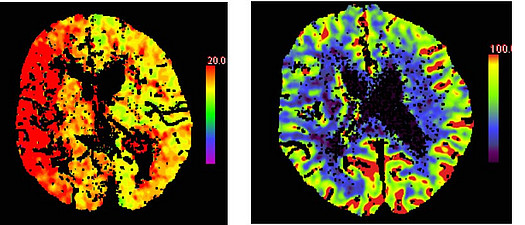

Hier werden in mehreren Schichten Röntgenaufnahmen meist vom Kopf der Patient:innen gemacht, es kann aber der gesamte Körper untersucht werden. Während das CT brummt wird gerade eine Patientin zweimal hintereinander durch die Gantry (Röhre) gefahren. Dabei wird innerhalb weniger Sekunden ein Datensatz des Kopfes erstellt, der in allen Raumebenen rekonstruiert werden kann. In nicht mal zehn Minuten ist die Untersuchung bereits abgeschlossen und auf dem Monitor sind in verschiedenen Graustufen das Gehirn, die Knochen und das Gehirnwasser zu sehen. Dabei sind nicht alle Bilder nur schwarz und weiß. Bei der sogenannten CT- Perfusionsbildgebung kann mit Hilfe von bunten Bildern bei Schlaganfällen abgeschätzt werden, wie gut einzelne Hirnareale mit Blut versorgt werden. Hierzu dienen unterschiedliche Parameter wie TTP (Time to Peak), die misst, wie lange es dauert, bis Kontrastmittel im Gehirn anflutet.